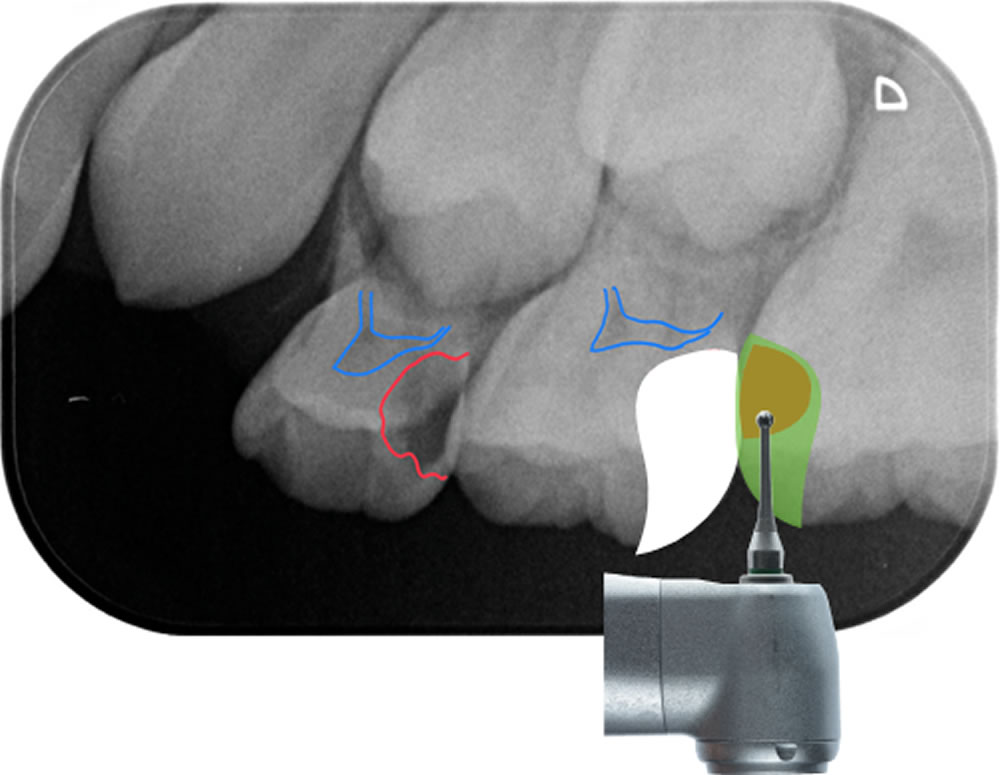

むし歯の切削

表面麻酔を十分置いたあと、極細の注射針で浸潤麻酔をしました。一番大きいむし歯がある左上Dから、むし歯治療を開始しました。むし歯の穴の大きさに合った切削器具を使用します。

また、う蝕検知液というむし歯の部分だけを青く染めてむし歯を取り除く工夫を行い、健康な歯は削らないよう心がけます。う蝕検知液で染める→削るを繰り返し、徹底的にむし歯を除去し、う蝕検知液で染まらなくなったら取り除き終わった証拠です。

青点線:保存することができた健全歯質

同様の治療を左上E、左上6番にも行います。左上6番は永久歯で、第一大臼歯、6歳臼歯とも呼ばれ永久歯で一番最初に生えてくる永久歯です。咬み合わせを安定させるためにとても大切なだけではなく、人生で一番長く使わなければならない歯です(あと100年は使わなければならない歯です!!)。

咬む面はできれば削らずに、そのままの状態で残したいと考えていました。今回のケースでは無事、左上6番の辺縁隆線と呼ばれる写真青点線部を保存することができました。また、3歯とも神経までは到達しなかったので、神経は残せそうです。